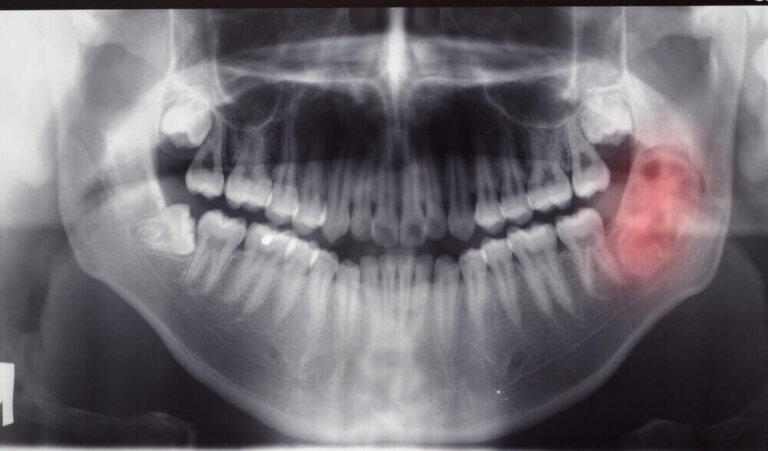

Afin de disposer d’un maximum d’informations sur les tumeurs et les kystes de la mâchoire, des tests de diagnostic tels que des radiographies, des scanners ou des orthopantomographies seront demandés.